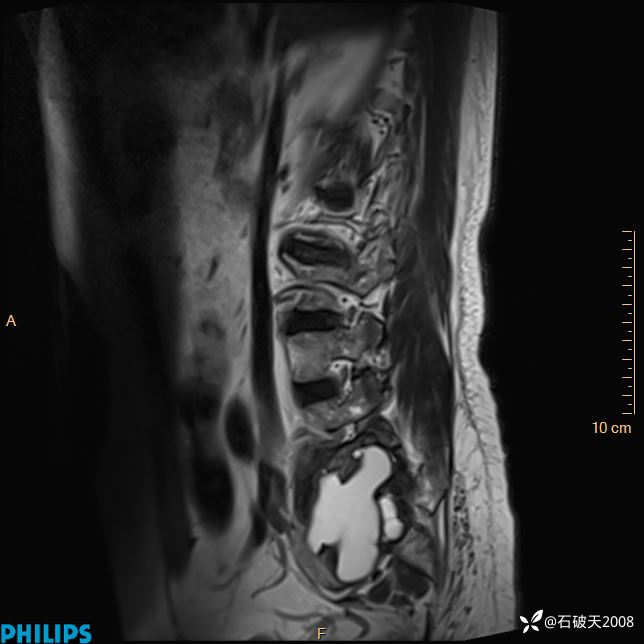

2023年3月份MRI影像

T2矢状位

T2矢状位压脂

T1矢状位